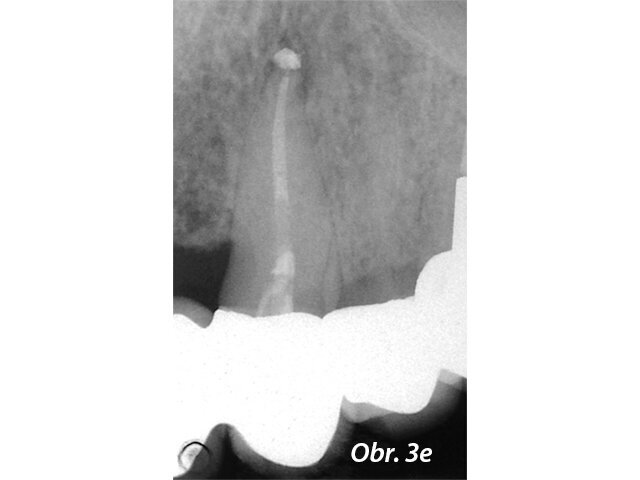

Překrytí pulpy

V posledních letech se stala populární terapie zachování vitální pulpy. Běžným materiálem pro překrytí pulpy byl hydroxid vápenatý, ale MTA vykazuje lepší výsledky v biokompatibilitě a úspěšnosti (Aguilar a Linsuwanont 2011). Případy s rozsáhlým kariézním nálezem mohou být úspěšně ošetřeny částečnou pulpotomií a překrytím MTA, což zachová pulpu vitální (obr. 1a–e).

Postoperační RTG zobrazující překrytí pulpy s MTA